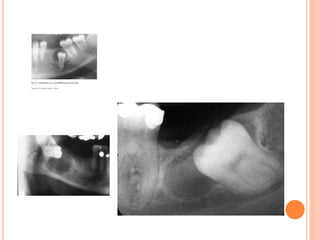

Dentigerous cyst

RADIOGRAPHIC FEATURES:-  Threeradiological variations of dentigerous cyst are seen radiographically:-  Central type:- In this type the crown is enveloped symmetrically.  Lateral type:- This type of radiographic appearance results from dilation of follicles on one aspect of crown.  Circumferential type:- This type results when the follicle expands in a manner in which the entire tooth appears to be involved by the cyst